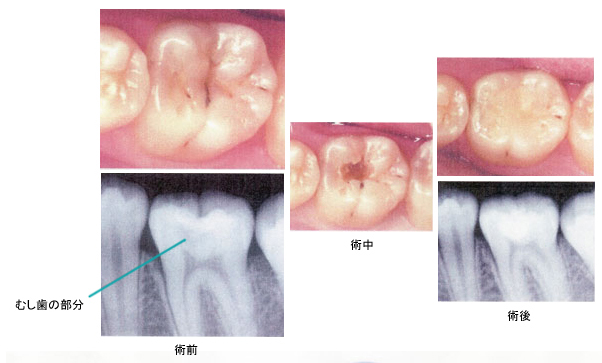

CASE 01 小さいむし歯

【病態】

【治療(過程)】